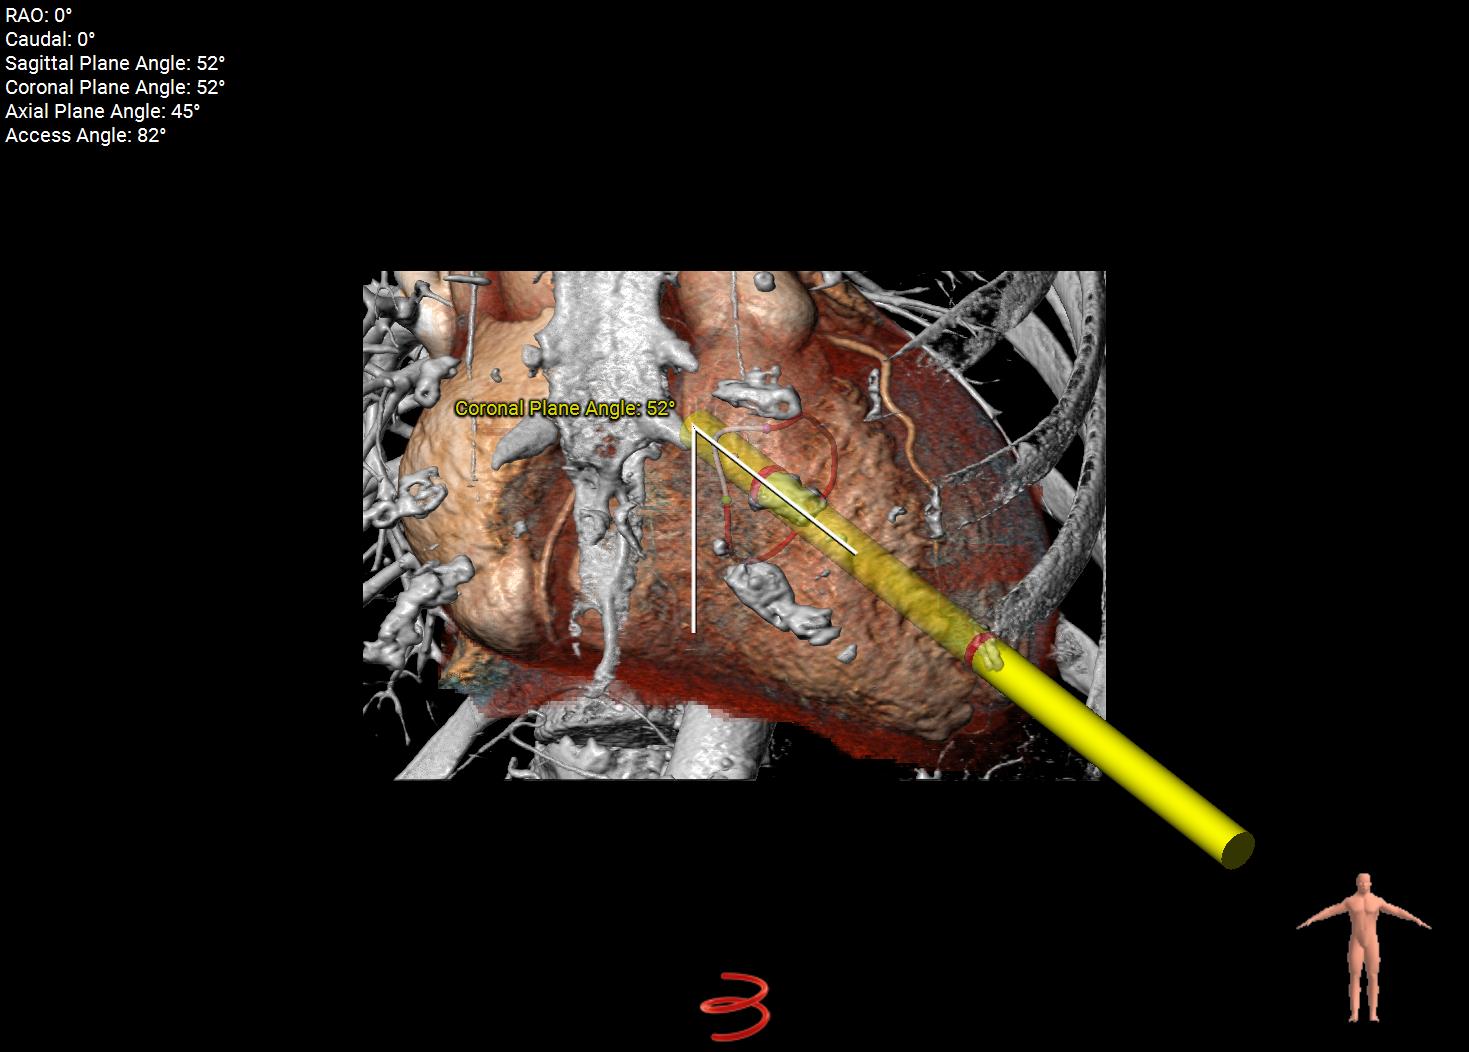

Planning software like 3mensio Structural Heart can can streamline TMVR planning by providing accurate annular sizing, neo-LVOT area prediction, assessment of annular and sub-annular calcification, and simulation of both transapical and transseptal access paths. This comprehensive imaging and planning workflow enables device selection, positioning, and risk management, particularly in anatomically challenging cases.